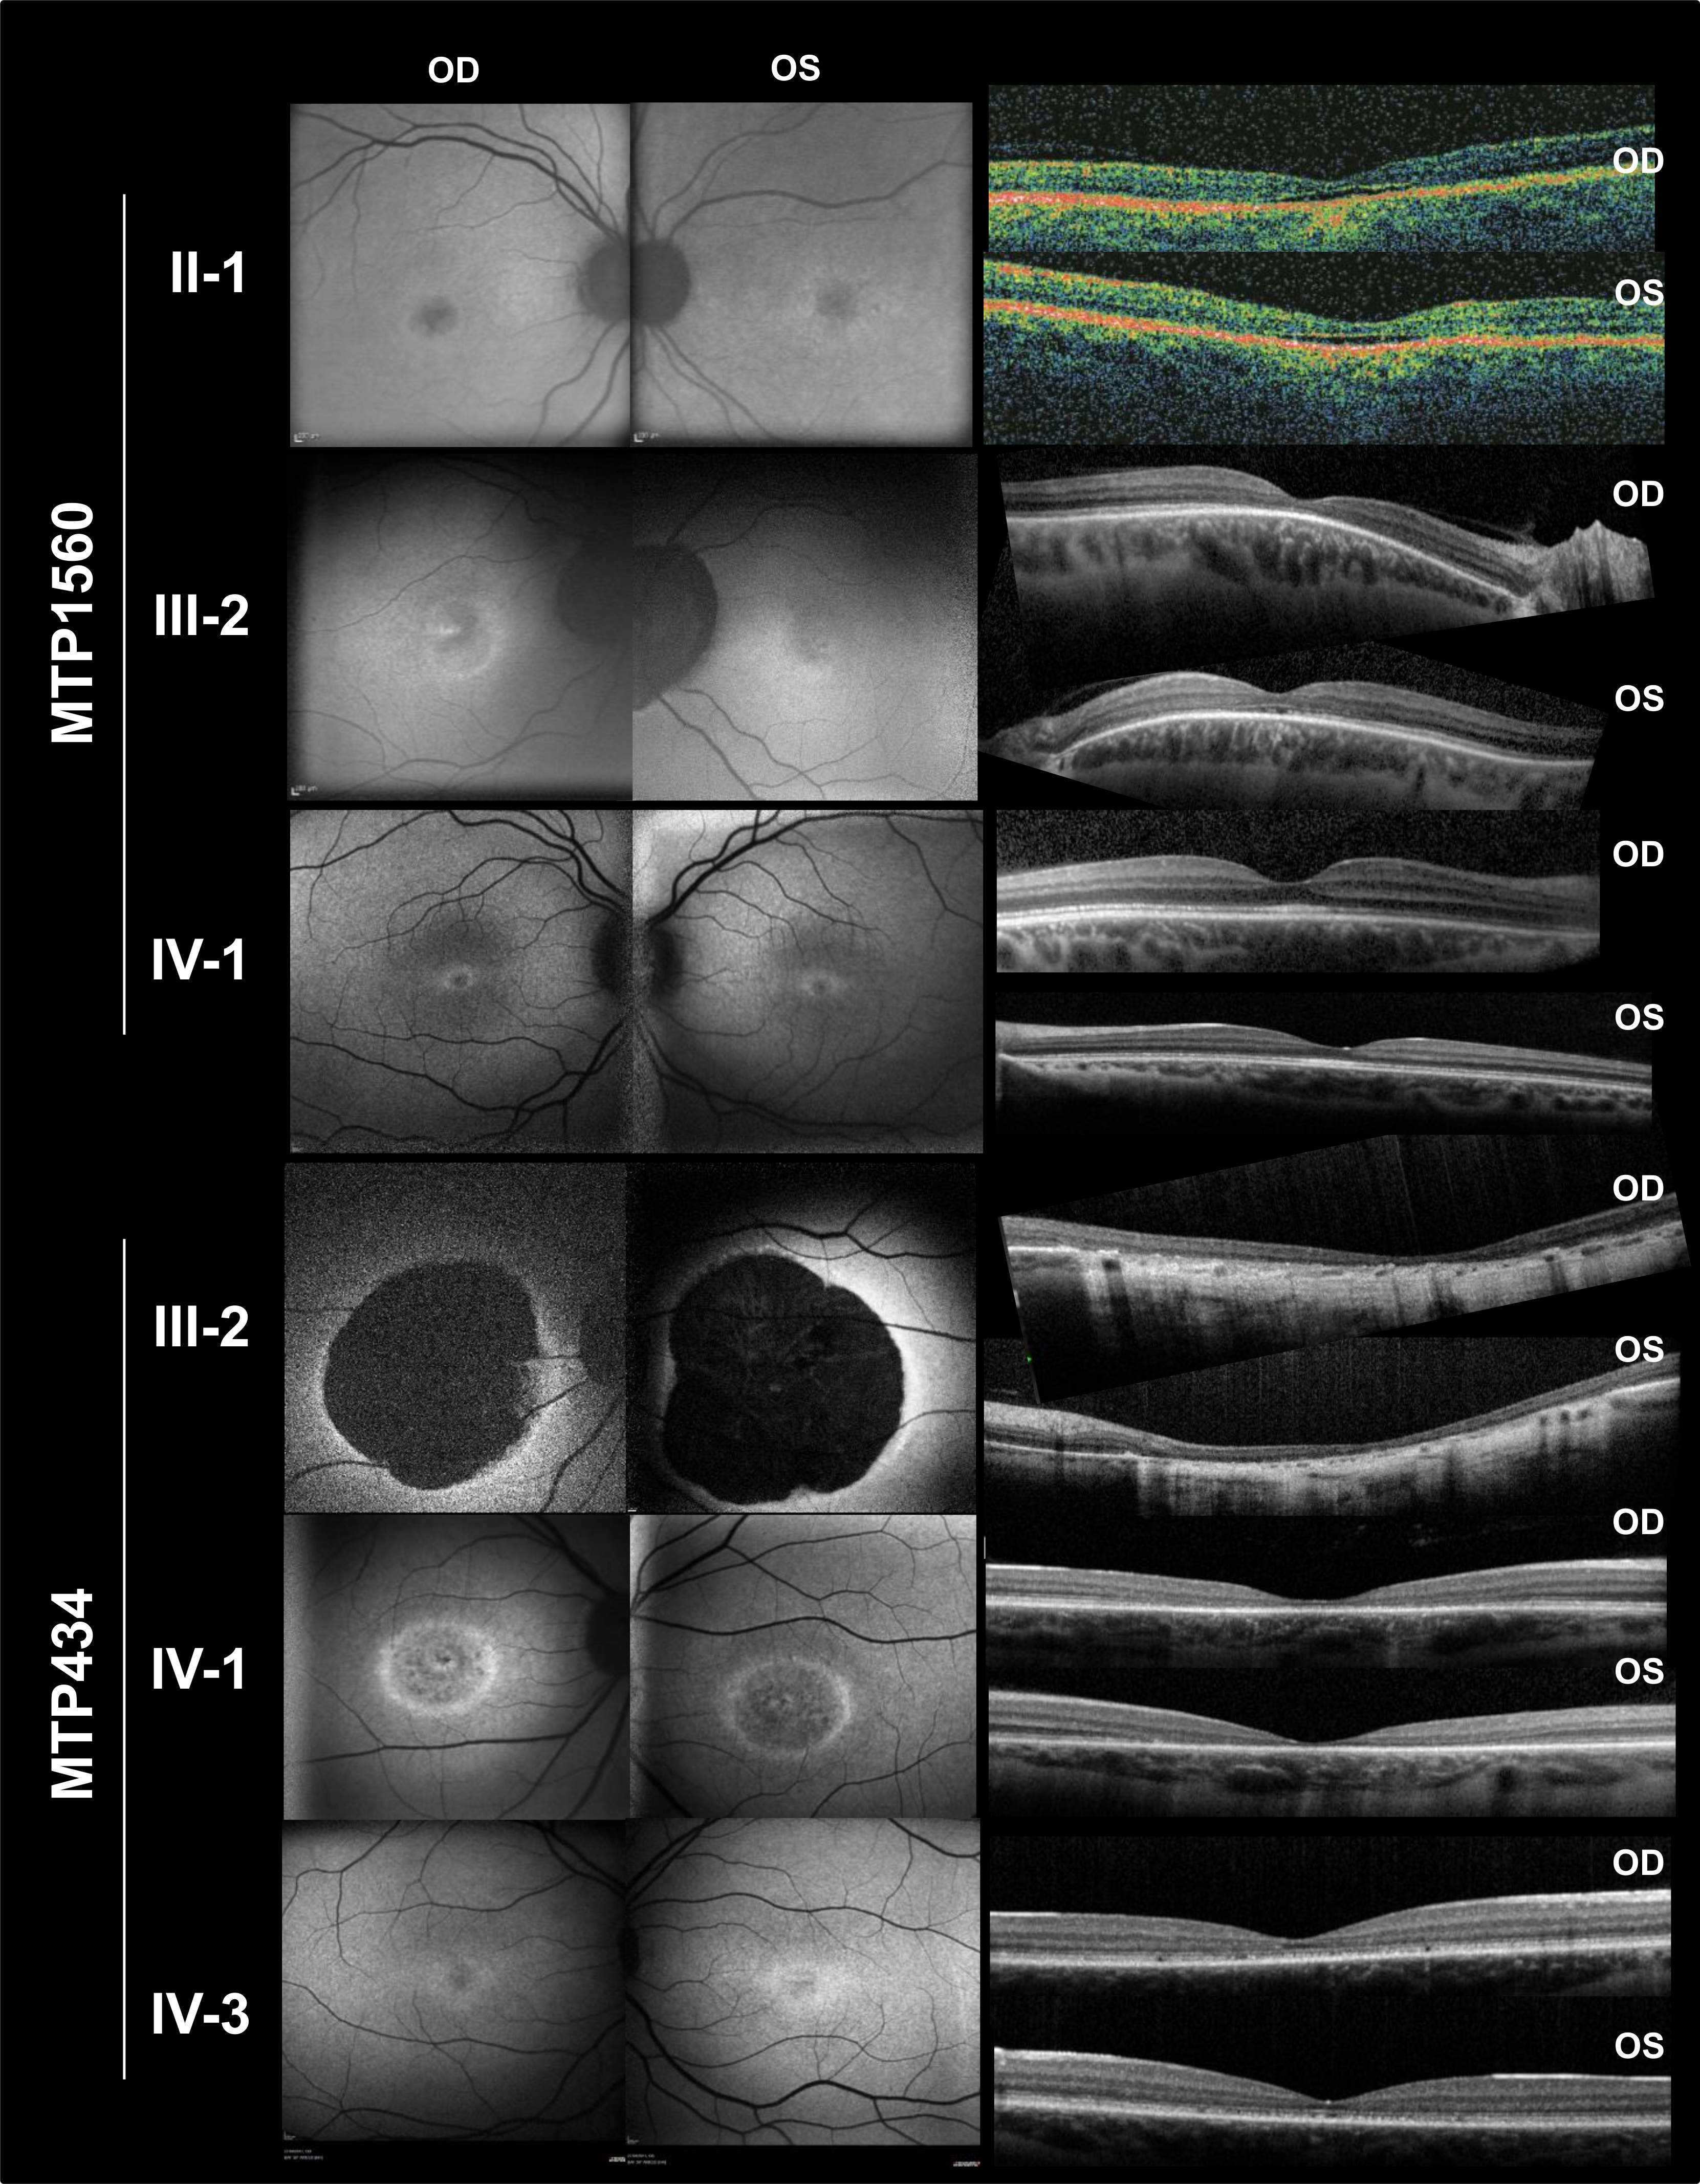

Figure 4. Fundus autofluorescence (FAF) photographs and spectral-domain optical coherence tomography (OCT) scans of patients with GUCA1A mutations. Family MTP434 FAF, mild perifoveal hyperautofluorescence in IV:3; small, round, hypoautofluorescent lesion in

IV:1; and no autofluorescence in the macular lesion in III:2. Family MTP434 OCT, complete (in IV:1) or near-complete (in III:2)

foveal atrophy; a thinned ellipsoid zone remained present in IV:3. Family MTP1560 FAF, moderate perifoveal autofluorescence

in IV:1, fovea moderately hypoautofluorescent in III:2 and II:1, and normal autofluorescence in the peripheral retina for

the three patients. Family MTP1560 OCT, thickened ellipsoid zone in the fovea in IV:1, absent ellipsoid zone with thinning

of the outer nuclear layer in the fovea in III:2, and partial foveal atrophy with a hyporeflective zone in both eyes in II:1.

OD, oculus dexter (right eye); OS, oculus sinister (left eye).